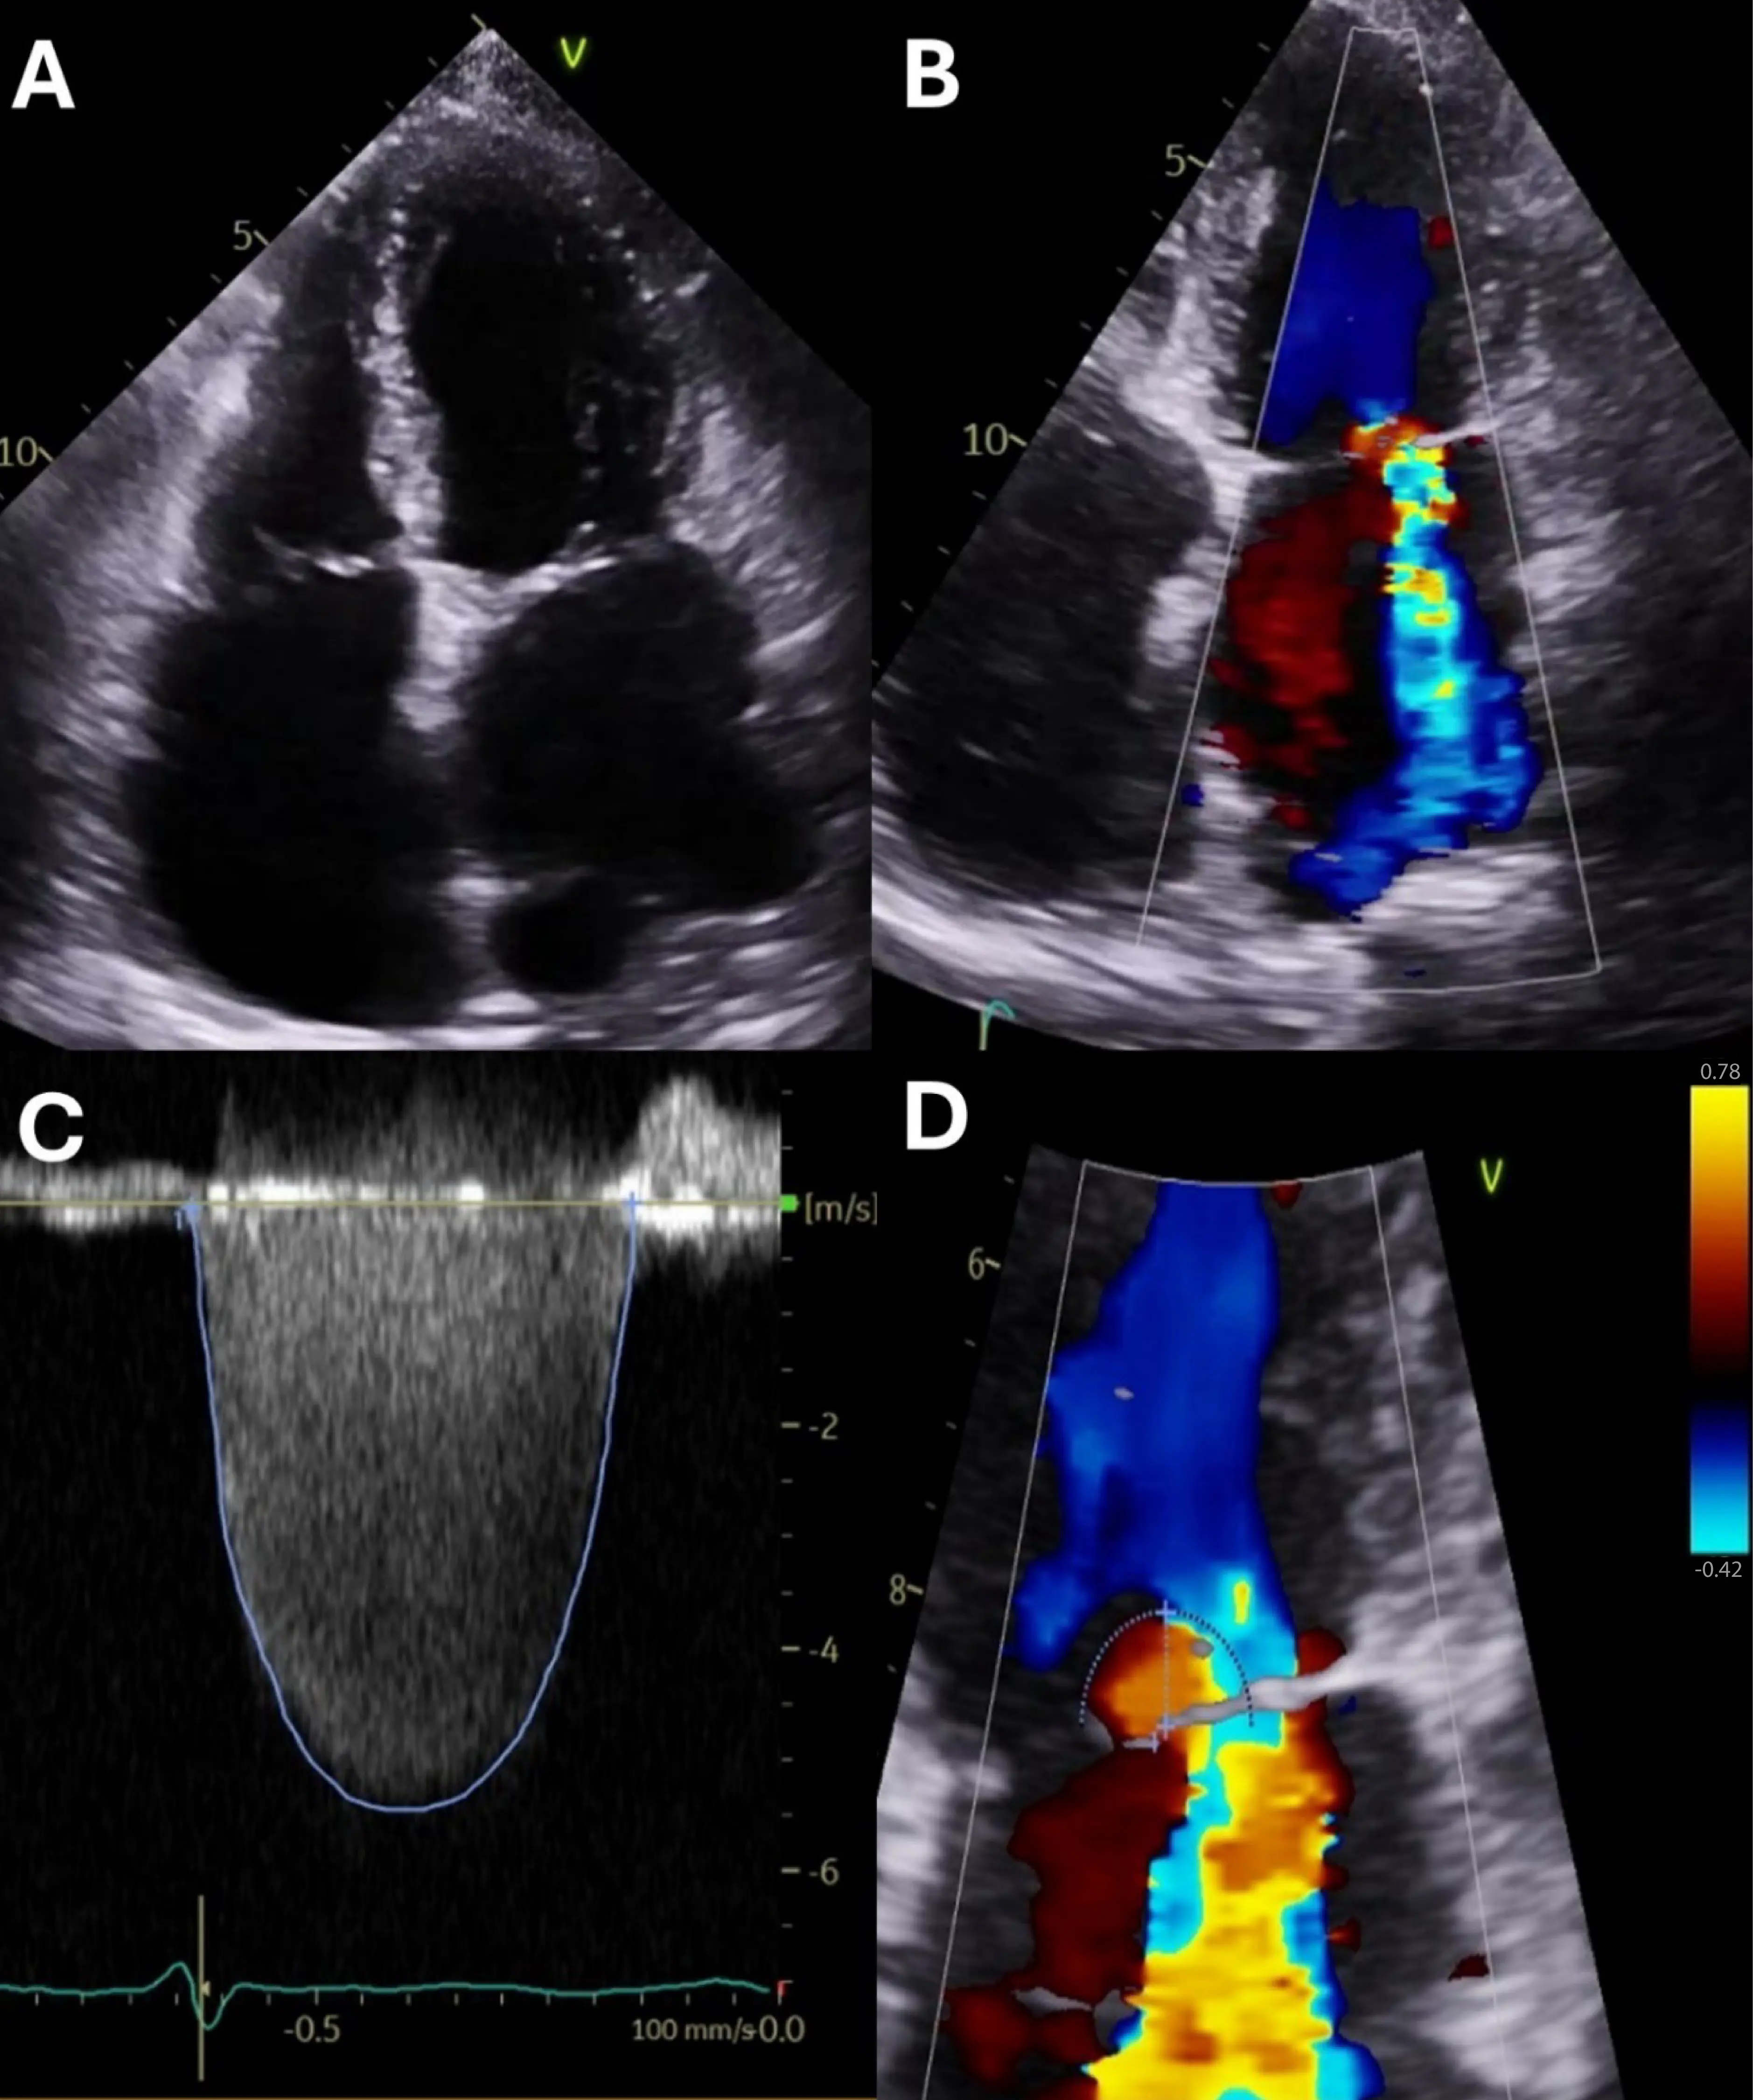

Despite these guidelines, accurately quantifying FMR remains challenging. The regurgitant orifice in FMR is often elliptical and dynamic, making the commonly used PISA method, which assumes a circular orifice, susceptible to underestimation [71]. Contemporary professional society guidelines generally agree on the importance of integrating quantitative and qualitative parameters when assessing FMR, differ in how rigidly EROA thresholds are applied, and how they inform TEER candidacy. The ACC/AHA guidelines define severe secondary MR using an EROA ≥ 0.40 cm2 (or regurgitant volume ≥ 60 mL) [37], consistent with primary MR, yet emphasize that intervention decisions, particularly TEER, should be guided by symptom burden, response to GDMT, and patient selection criteria derived from COAPT rather than by EROA alone [12]. In contrast, the ESC/EACTS guidelines adopt lower quantitative thresholds for severe FMR (EROA ≥ 0.20 cm2 or regurgitant volume ≥ 30 mL) [2]. The differences in EROA thresholds reflect the challenging aspects of MR assessment, given differences in mechanistic factors and the load-dependent nature of secondary MR, but both guidelines similarly stress comprehensive assessment and clinical context over isolated cutoffs. Recent studies suggest that an intermediate value of around 0.30 cm2 may better correlate with adverse outcomes and response to therapy [72,73]. The ASE/EACVI recommendations further reinforce this integrative approach, cautioning against reliance on a single parameter, such as EROA, and advocating multiparametric grading that incorporates ventricular size and function, regurgitant jet characteristics, and dynamic behavior [74]. Taken together, these documents are aligned in recognizing the limitations of rigid EROA thresholds in FMR and converge on the principle that TEER candidacy should be determined by a holistic evaluation of MR severity, ventricular remodeling, and clinical status rather than by any single quantitative metric. Figure 4 illustrates the multi-parametric transthoracic echocardiographic assessment used to grade severe AFMR, encompassing chamber enlargement, jet characteristics, and quantitative Doppler measurements.

Figure 4. Transthoracic Echocardiographic Assessment of Severe Atrial Functional Mitral Regurgitation. (A) Apical four-chamber view demonstrating severe bi-atrial enlargement with marked dilation and flattening of the mitral annulus, consistent with atrial functional mitral regurgitation. The numbers along the side (e.g., 5, 10) are depth markers (in mm). (B) Color Doppler imaging in the same view reveals a broad, centrally directed jet of severe mitral regurgitation. Red vs. blue represent opposite flow directions relative to the transducer (conventionally: red = toward, blue = away, depending on the machine’s color map and orientation). Yellow/orange/mosaic colors indicate aliasing and turbulent/high-velocity flow (velocity exceeding the Nyquist limit). (C) Zoomed color Doppler view focused on the regurgitant orifice, showing a proximal isovelocity surface area (PISA) radius of 0.8 cm, supportive of significant regurgitant flow. The y-axis shows velocity (units shown as m/s). The horizontal baseline (0 m/s) separates flow directions (above vs. below baseline). The outlined envelope/contour (blue tracing) marks the spectral Doppler envelope used for measurement (e.g., peak velocity and/or velocity-time integral). The ECG trace at the bottom provides timing within the cardiac cycle. (D) Continuous-wave Doppler tracing across the mitral valve reveals a dense, holosystolic MR signal with a peak velocity of 5.5 m/s, consistent with elevated regurgitant volume and pressure gradient. This corresponds to an effective orifice regurgitant area (EROA) of 0.31 cm2. The dashed circular/semicircular outline highlights the proximal flow convergence/isovelocity contour. The straight line/arrow indicates the measured radius/distance from the flow origin to the aliasing boundary. The vertical color bar at the right is the velocity color scale, showing the range and direction of encoded velocities (i.e., the Nyquist limits and the color mapping).